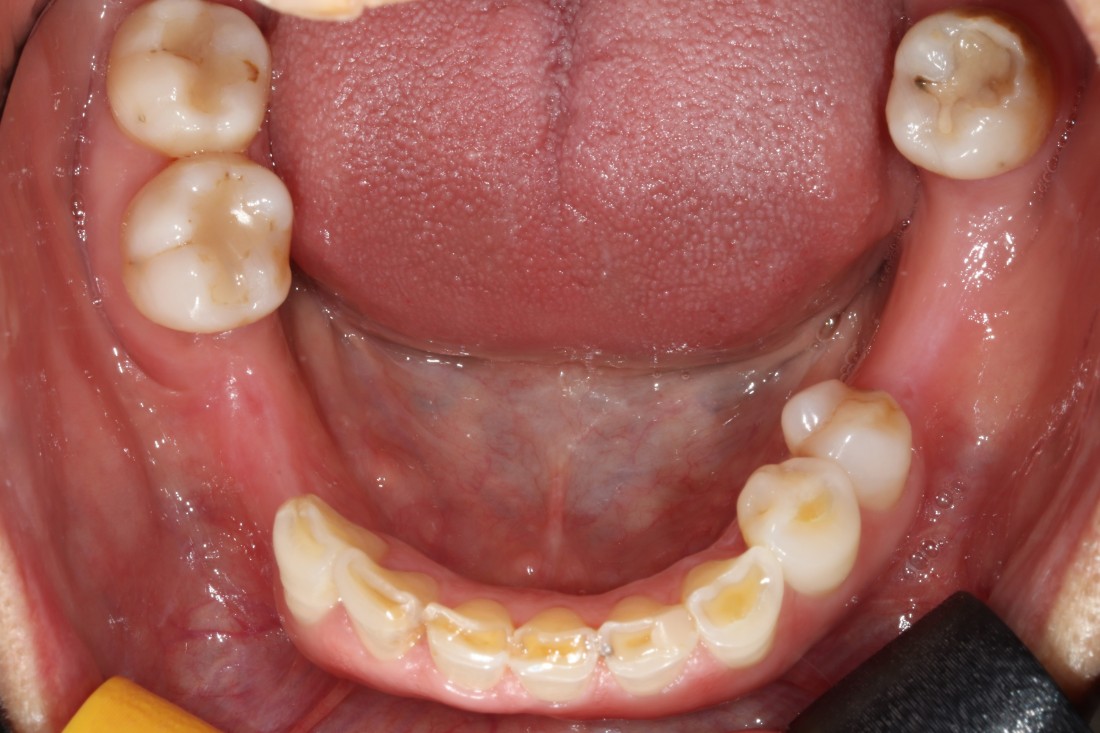

우리가 치아를 나눌 때에

윗니 (상악) / 아랫니 (하악) 이렇게

간단하게 구분을 하는데요.

일반적으로 상악임플란트는

하악에 비해 잇몸뼈가 얇은 경우가 많고

예뻐야 하는 심미적인 부분도

담당하기 때문에

특별히 신경써서 상악임플란트 수술경험이

풍부한 구강외과 전문의에게

진료받는 것을 추천드립니다.